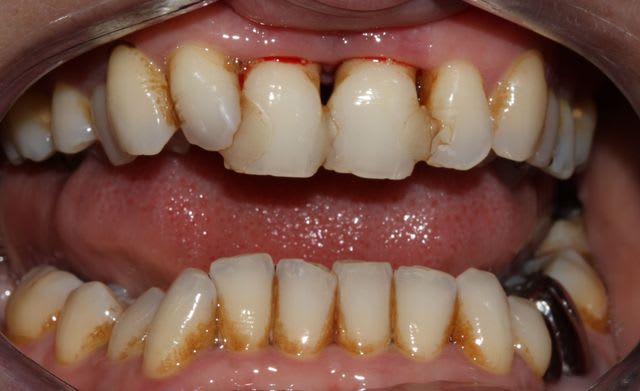

-21 (très) mal barrée ... et 11 aussi

Photos avant et après surfaçage .

12/13 /22/23 alvéolysé de 50%

Implant bien entendu à oublier